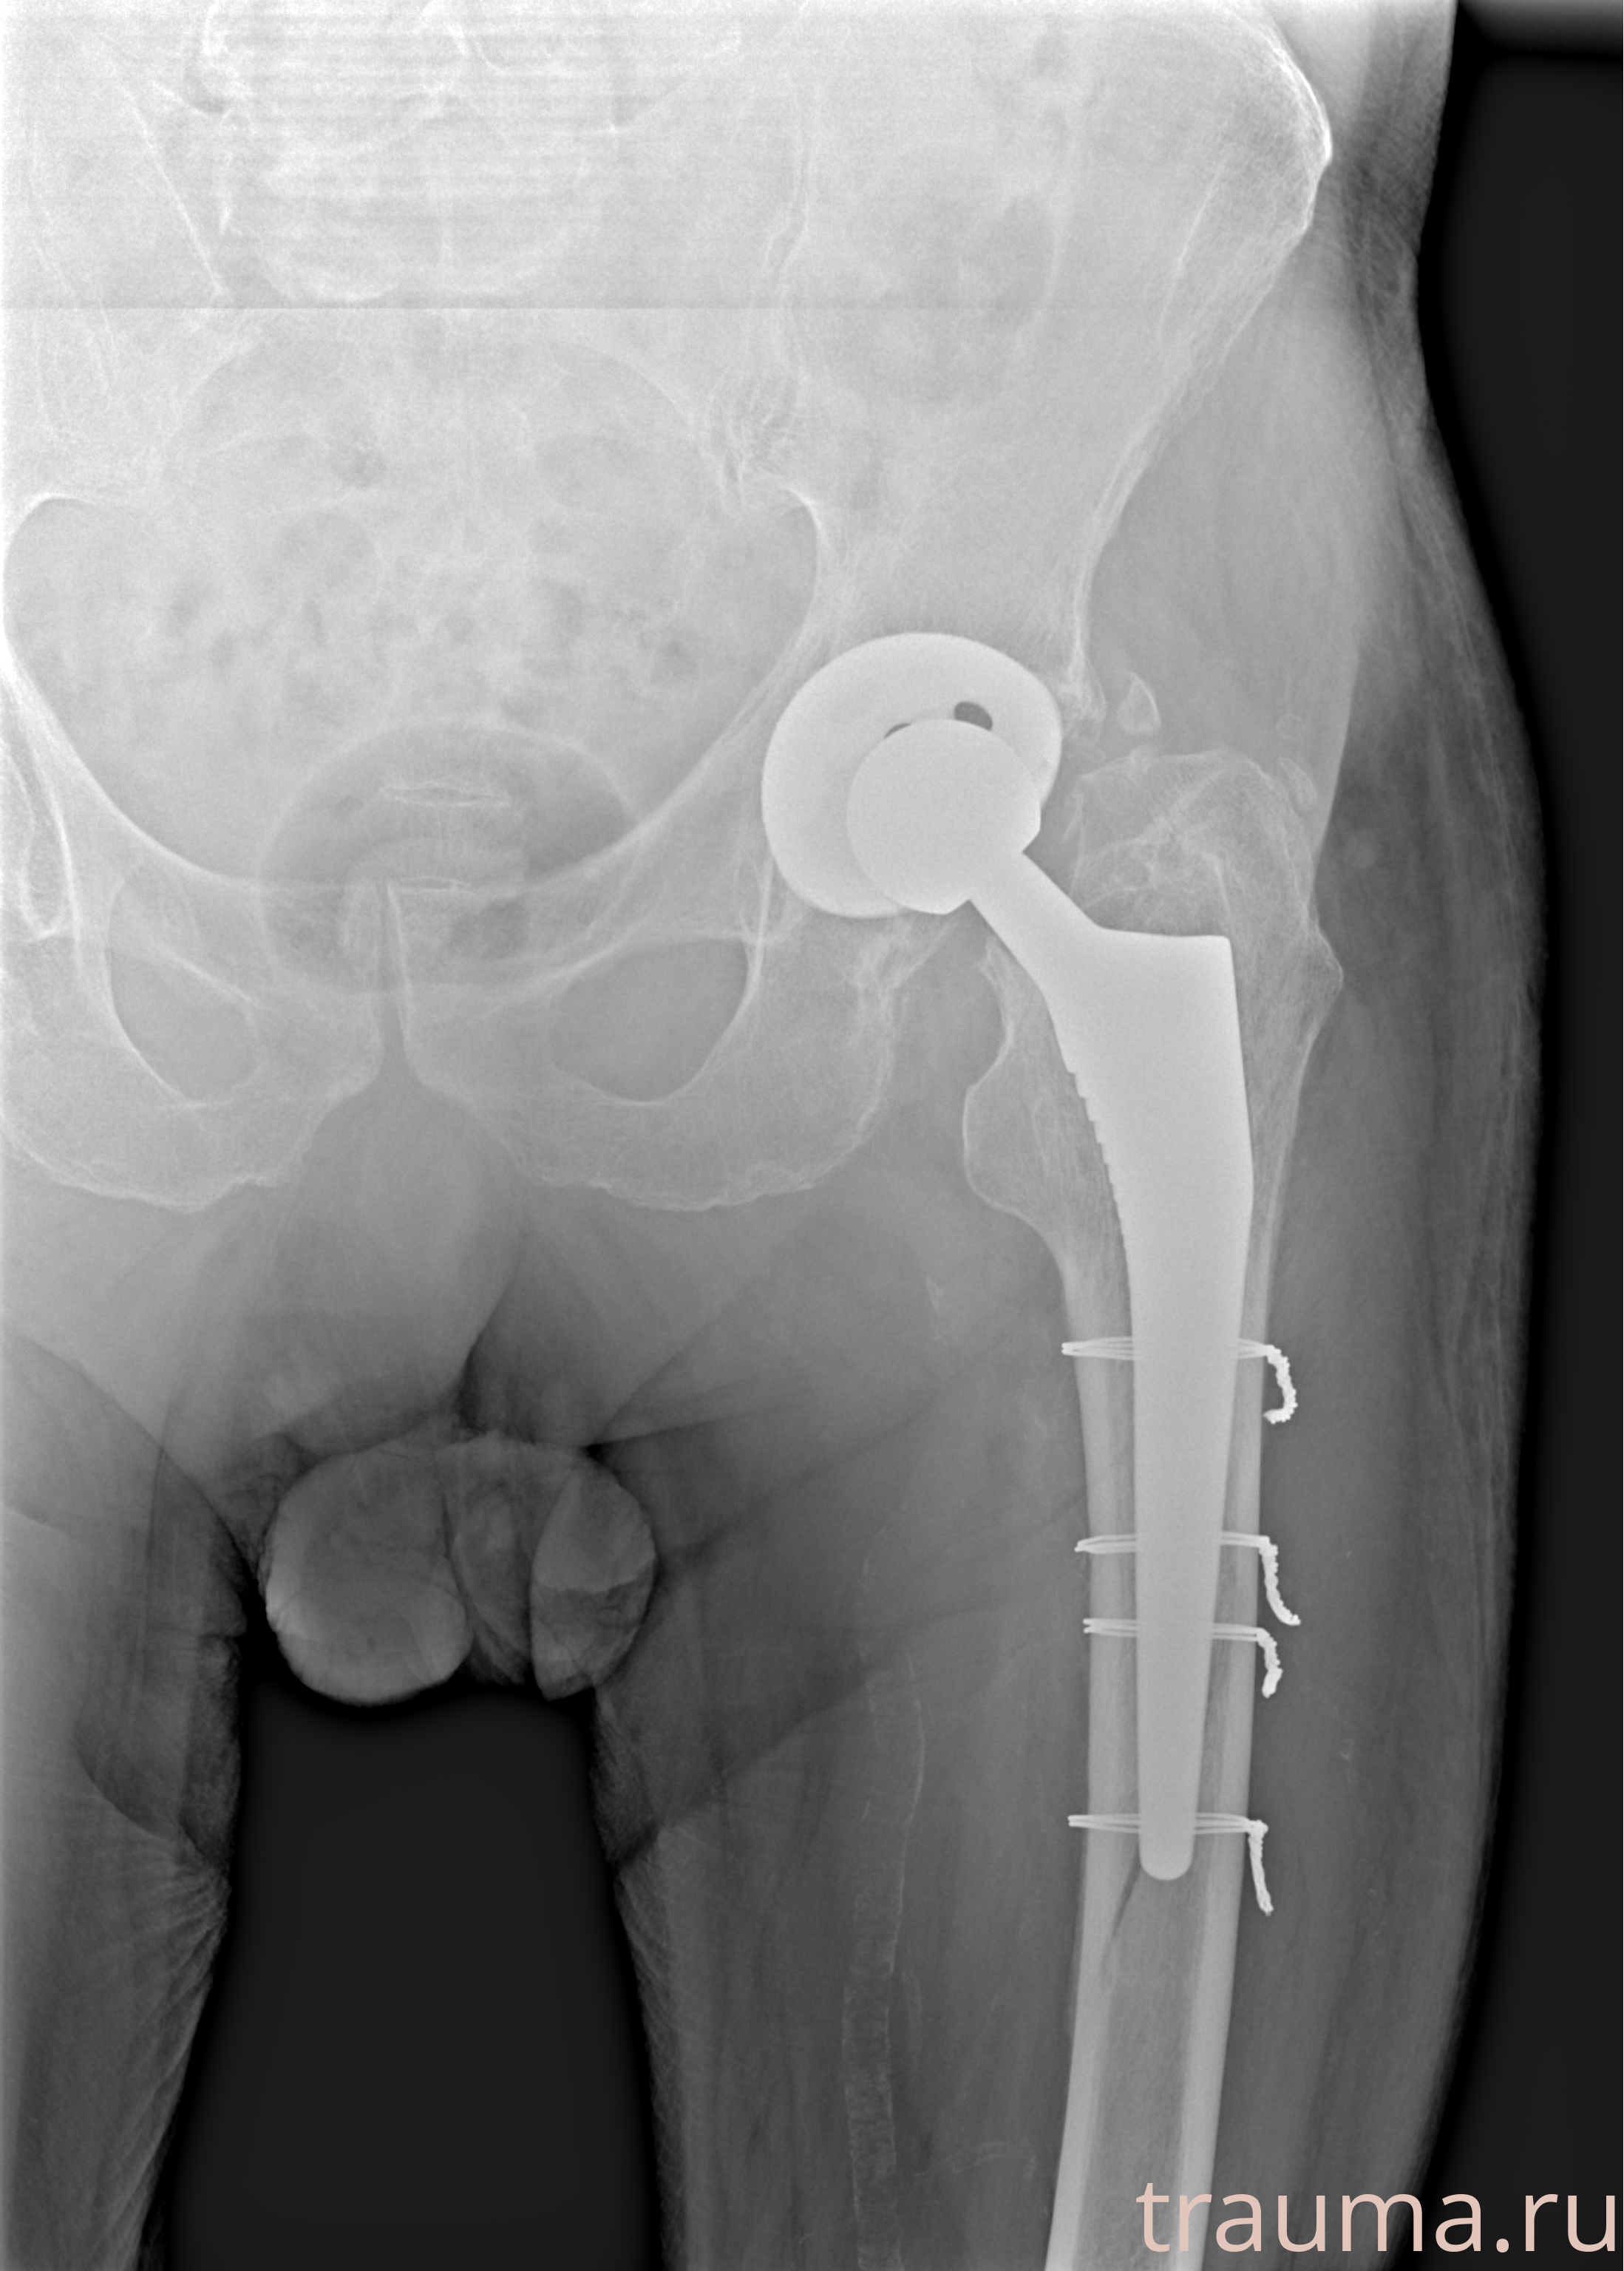

Рентгенограммы

Рентген на дому: по вашему адресу приезжает врач-рентгенолог, травматолог-ортопед с мобильным рентгеновским аппаратом, проводит диагностику травмы или заболевания, делает необходимые рентгенограммы, дает рекомендации по дальнейшему лечению. Получить качественные снимки в домашних условиях возможно благодаря уникальной методике, разработанной МосРентген Центром для института  Склифосовского